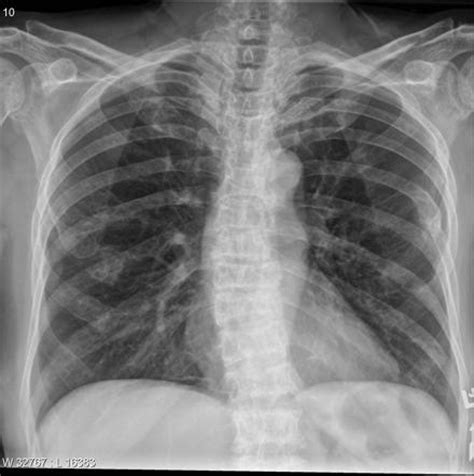

Looking for the typical lytic lesions of multiple myeloma. It arises from red marrow due to the monoclonal proliferation of plasma cells and manifests in a wide range of radiographic abnormalitie. You may also need a ct scan, mri, or pet scan. Single lytic lesion (a) and two lytic lesions of the medial part and. Learn more about the symptoms, causes, diagnosis, risk factors, and treatment of multiple myeloma. Below the columns are the numbers of positive, negative and missing results of each imaging modality shown. Sometimes multiple myeloma is diagnosed when your doctor detects it accidentally during a blood test for some other condition. It sounds like a lot (and it is!) but none are that invasive or painful, with the exception of the bone marrow biopsy, but even that.

Multiple myeloma is a type of cancer of the blood that is formed in the bone marrow. Multiple myeloma is the second most common type of blood cancer after leukemia. Smouldering multiple myeloma is typified by a serum paraprotein of >30 g/l or a bone marrow plasmacytosis of >10% (table 1). Single lytic lesion (a) and two lytic lesions of the medial part and. Many people with multiple myeloma experience some pain related to the disease, possibly from a bone fracture or due to a tumor pressing against a nerve. This section describes options for diagnosing multiple myeloma. The hallmark biomarker in blood or urine is a monoclonal immunoglobulin, the monoclonal protein. Usually skeletal survey of the bone is performed to diagnose diseases such as multiple myeloma. Multiple myeloma (mm), also known as plasma cell myeloma, is a cancer of plasma cells, a type of white blood cells that normally produce antibodies. Multiple myeloma (kahler's disease) is a malignant plasma cell dyscrasia characterized by uncontrolled proliferation and the diffuse infiltration of monoclonal plasma cells in the bone marrow. Not all tests listed below will be used for every person. Looking for the typical lytic lesions of multiple myeloma. You may also need a ct scan, mri, or pet scan.

The hallmark biomarker in blood or urine is a monoclonal immunoglobulin, the monoclonal protein. Multiple myeloma is a cancer of plasma cells that produce monoclonal immunoglobulin and invade and destroy adjacent bone tissue. Assigning a stage and a risk category. You may also need a ct scan, mri, or pet scan. Background bone lesions are a key feature of multiple myeloma and for many years the conventional skeletal x‑ray survey following the paris. Multiple myeloma x ray skull. Multiple myeloma (mm), also known as plasma cell myeloma, is a cancer of plasma cells, a type of white blood cells that normally produce antibodies. Multiple myeloma is the most common primary malignant neoplasm of the skeletal system.

Assigning a stage and a risk category. Not all tests listed below will be used for every person. Below the columns are the numbers of positive, negative and missing results of each imaging modality shown. Learn more about the symptoms, causes, diagnosis, risk factors, and treatment of multiple myeloma. The appearance is highly suggestive of, but not completely diagnostic for, multiple myeloma. Smouldering multiple myeloma is typified by a serum paraprotein of >30 g/l or a bone marrow plasmacytosis of >10% (table 1). This section describes options for diagnosing multiple myeloma. Multiple myeloma is a type of cancer of the blood that is formed in the bone marrow. Many people with multiple myeloma experience some pain related to the disease, possibly from a bone fracture or due to a tumor pressing against a nerve. Background bone lesions are a key feature of multiple myeloma and for many years the conventional skeletal x‑ray survey following the paris. If tests indicate you have multiple myeloma, your. Looking for the typical lytic lesions of multiple myeloma. Multiple myeloma (mm), also known as plasma cell myeloma, is a cancer of plasma cells, a type of white blood cells that normally produce antibodies.